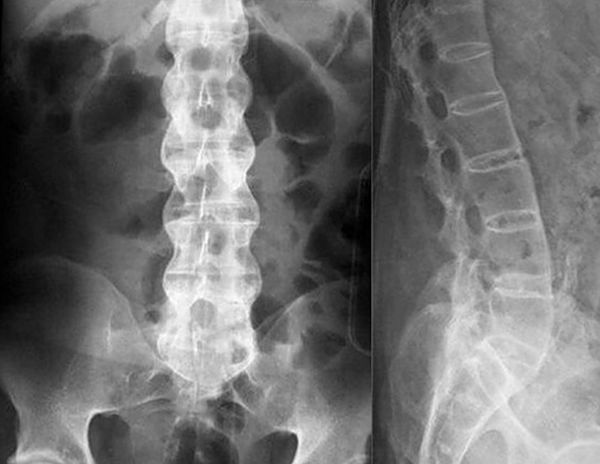

Рентген пояснично-крестцового отдела позвоночника

Одним из наиболее востребованных диагностических исследований, широко используемым в клинической практике, является рентген пояснично-крестцового отдела позвоночника.

Кратковременное действие рентгеновского излучения не причиняет пациенту вреда, зато позволяет изготовить снимки, отчетливо отображающие дефекты и патологические изменения костно-хрящевых структур.

Патологии мягких тканей различимы не так ярко, однако опытный рентгенолог-диагност выявляет на изображениях очаги воспалений, опухолевые процессы и ряд других нарушений.

Оборудование

Исследование проводят в специально оборудованном кабинете клиники, где установлен рентгеновский аппарат. Рентген пояснично-крестцового отдела – это абсолютно безболезненная, не травматичная процедура, которая длится не более 15 минут. В зависимости от характера заболевания и цели исследования рентгенолог делает несколько снимков в разных проекциях и позах. Результат выдается в бумажном или электронном виде.